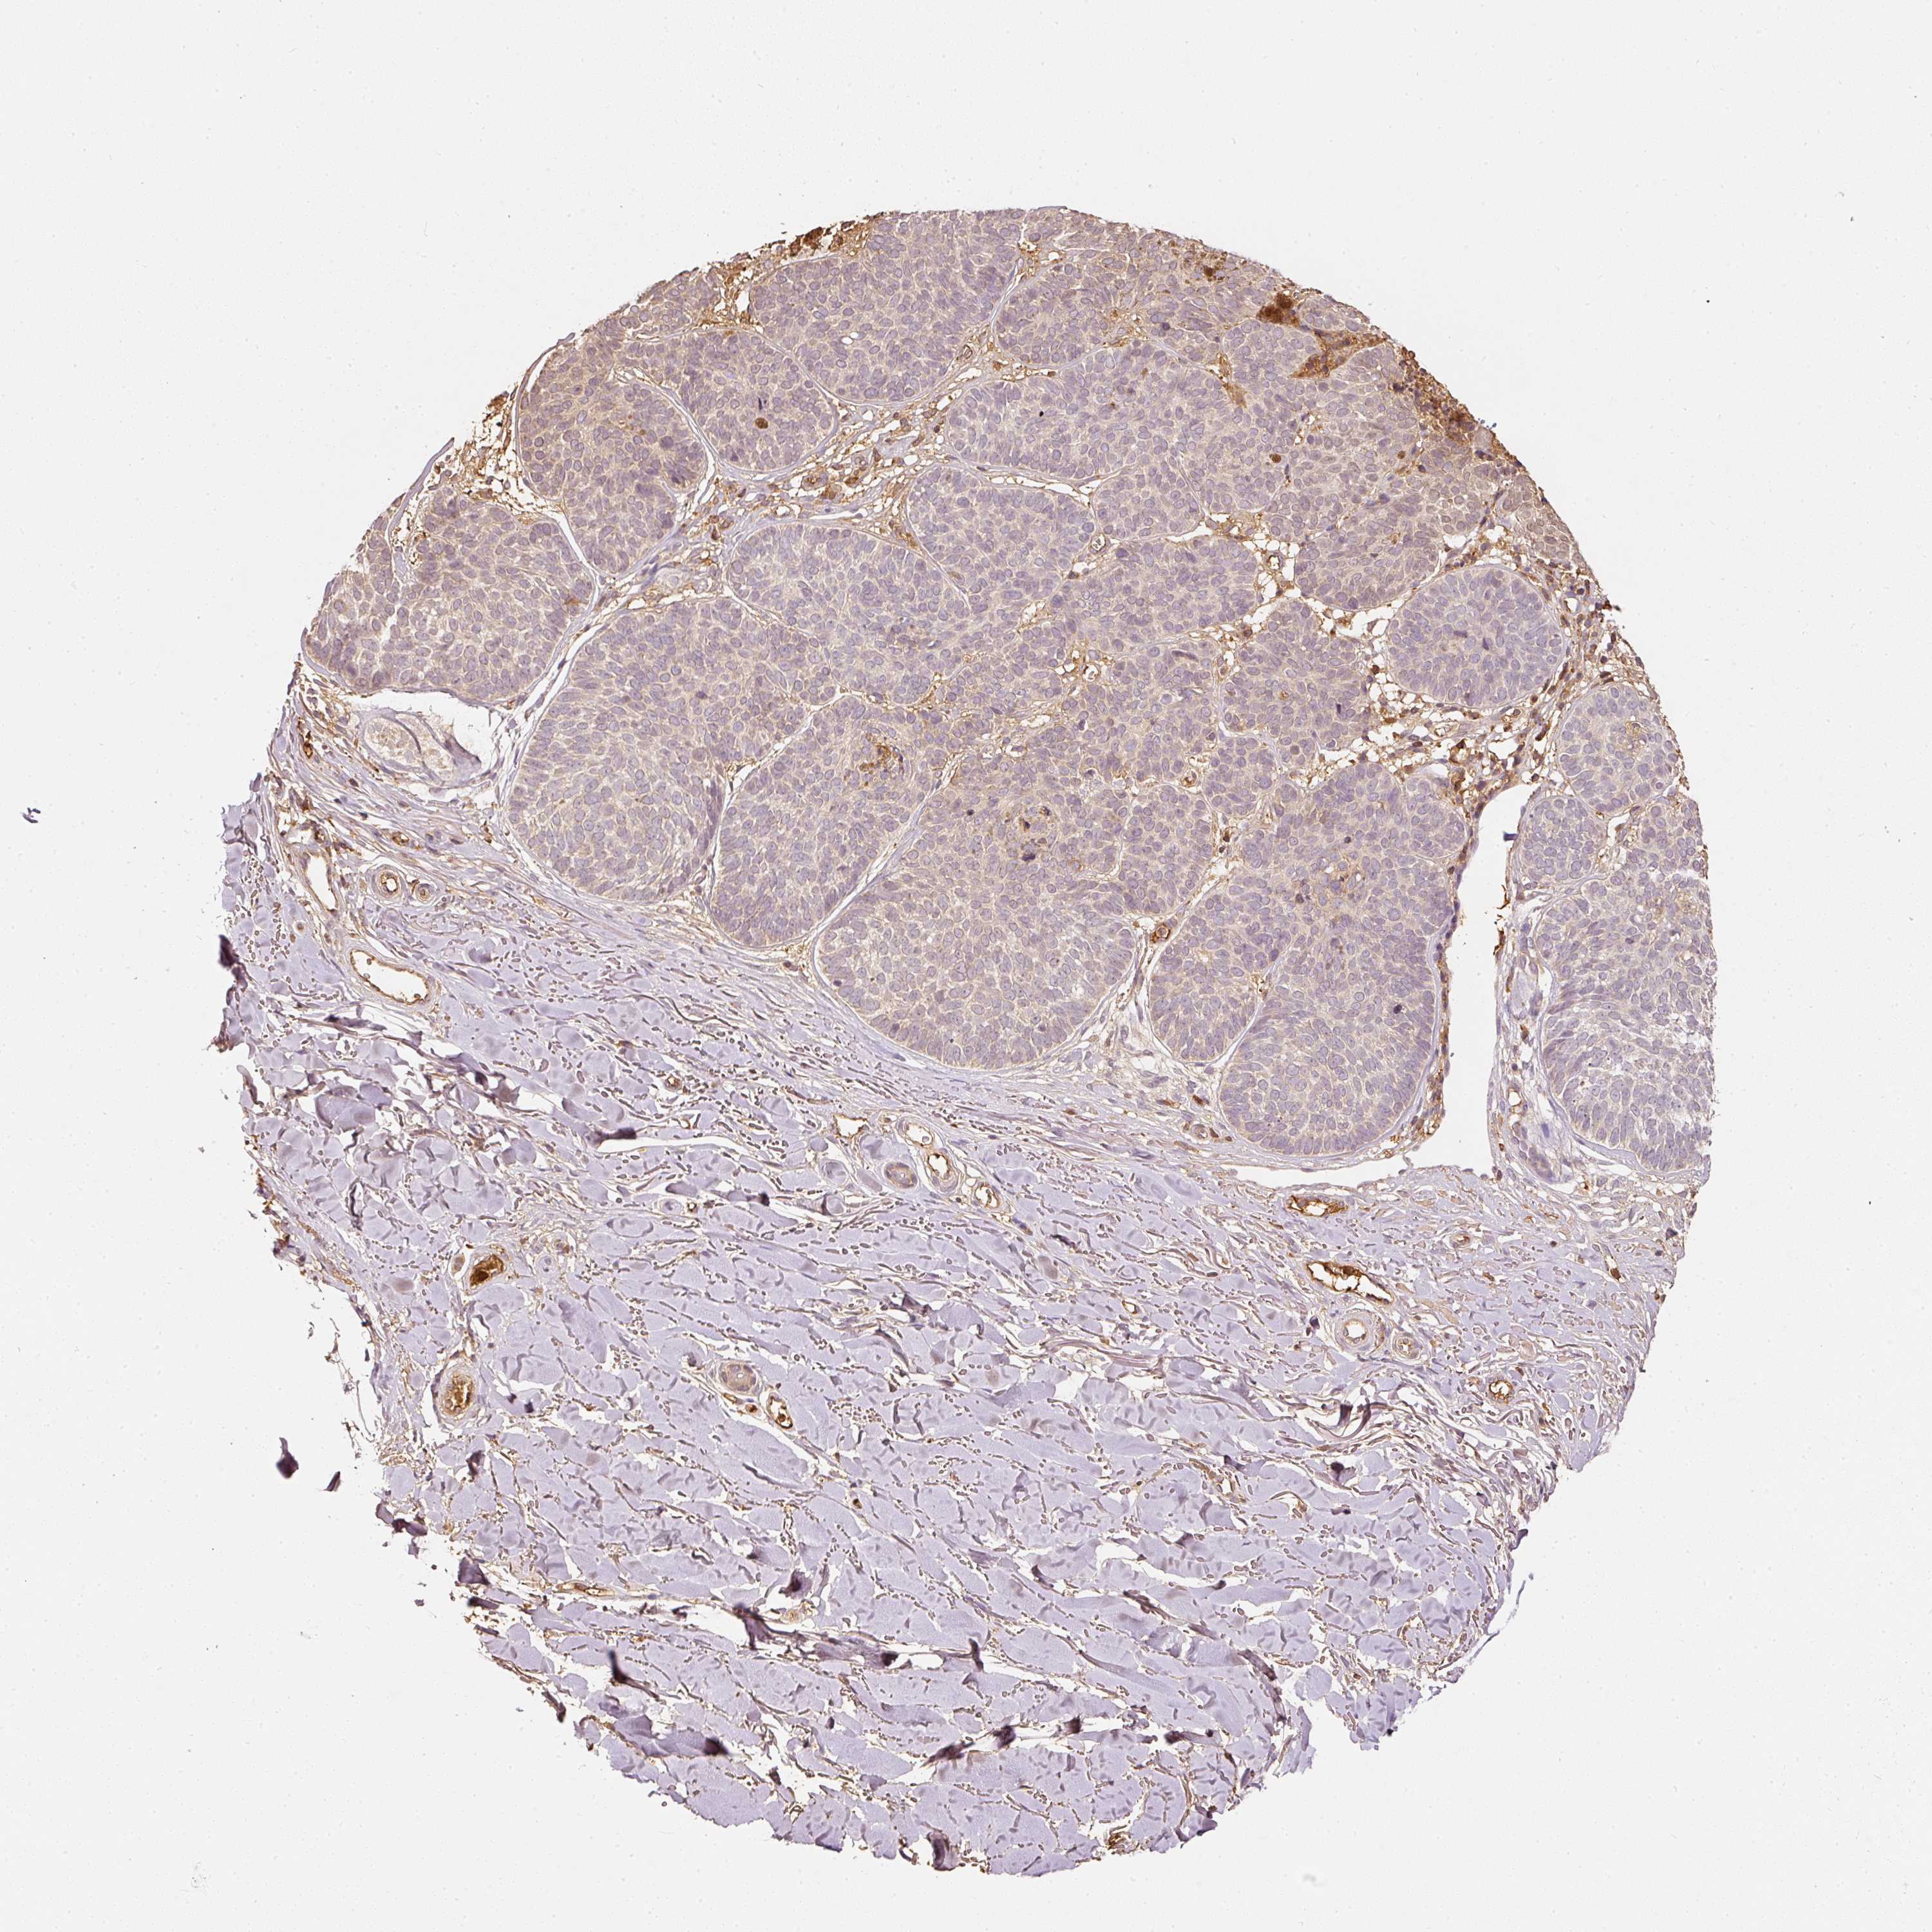

SKIN CANCER - Protein expressioni

A mouse-over function shows sample information and annotation data. Click on an image to view it in a full screen mode. Samples can be filtered based on level of antibody staining by selecting one or several of the following categories: high, medium, low and not detected. The assay and annotation is described here.

Each image is clickable and will lead to virtual microscopy that enables deeper exploration of all samples and also displays staining intensity scores, fraction scores and subcellular localization as well as patient and tissue information for each sample.

Antibody HPA019536

Squamous cell carcinoma, NOS